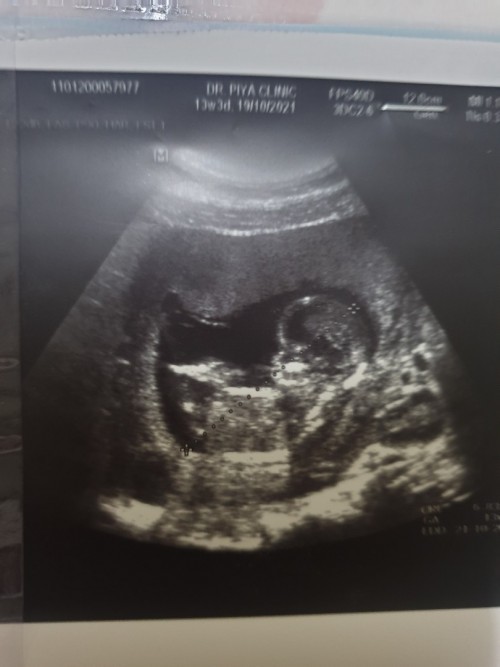

ตอนซาวต์ 13 week 1 วัน ชัดเจนมากแต่ตอนนี้ 15 week 6 วันแล้วค่ะ

ซาวตอน9สัปดาห์คะ ตอนนี้14สัปดาห์วันจันทร์นัดซาวอีกทีจ้า.